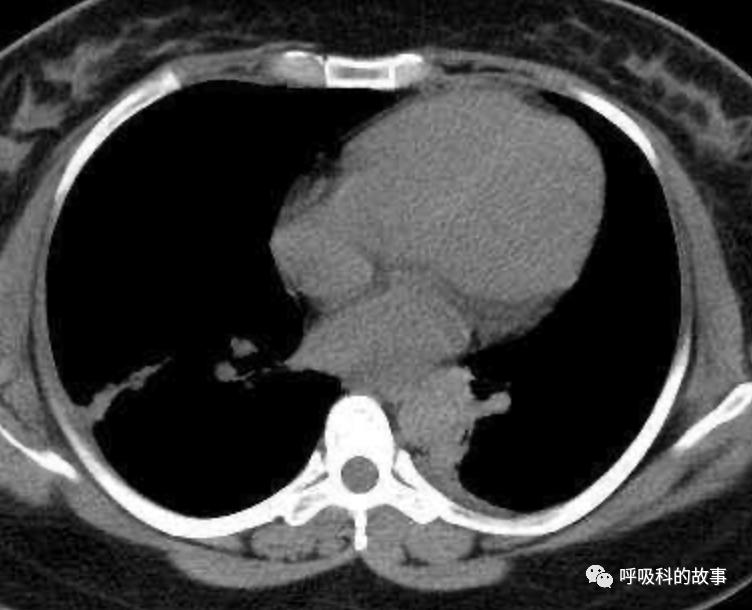

患者发热后行胸部CT检查(6月21日,住院第13天),可见两下肺有条片影,当时考虑是肺炎引起的发热。

可是在6月26日(往院第18天)仍持续发热的情况下复查肺部CT,肺部病灶已明显吸收了。那么患者发热的原因到底是什么呢?为什么患者高热的情况下血白细胞不升反降,C反应蛋白也没有明显增高?这个时候消化科医生也迷茫了,这可怎么办?于是请感染科和呼吸科医生一起会诊,共商计策。